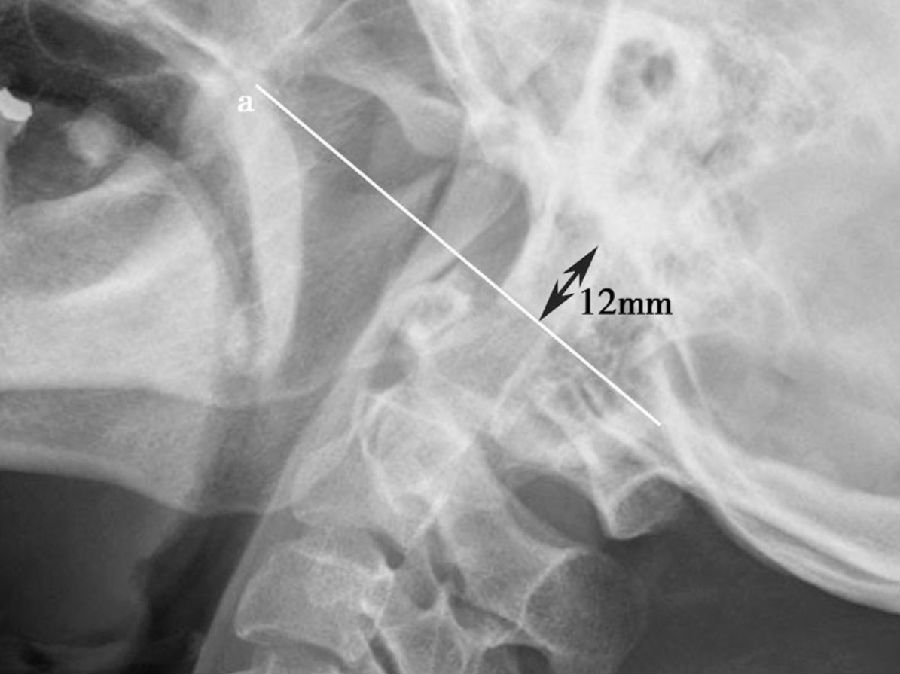

图7 颅底凹陷症齿突尖端位于Chamberlain线(a)上12mm(>5mm)。